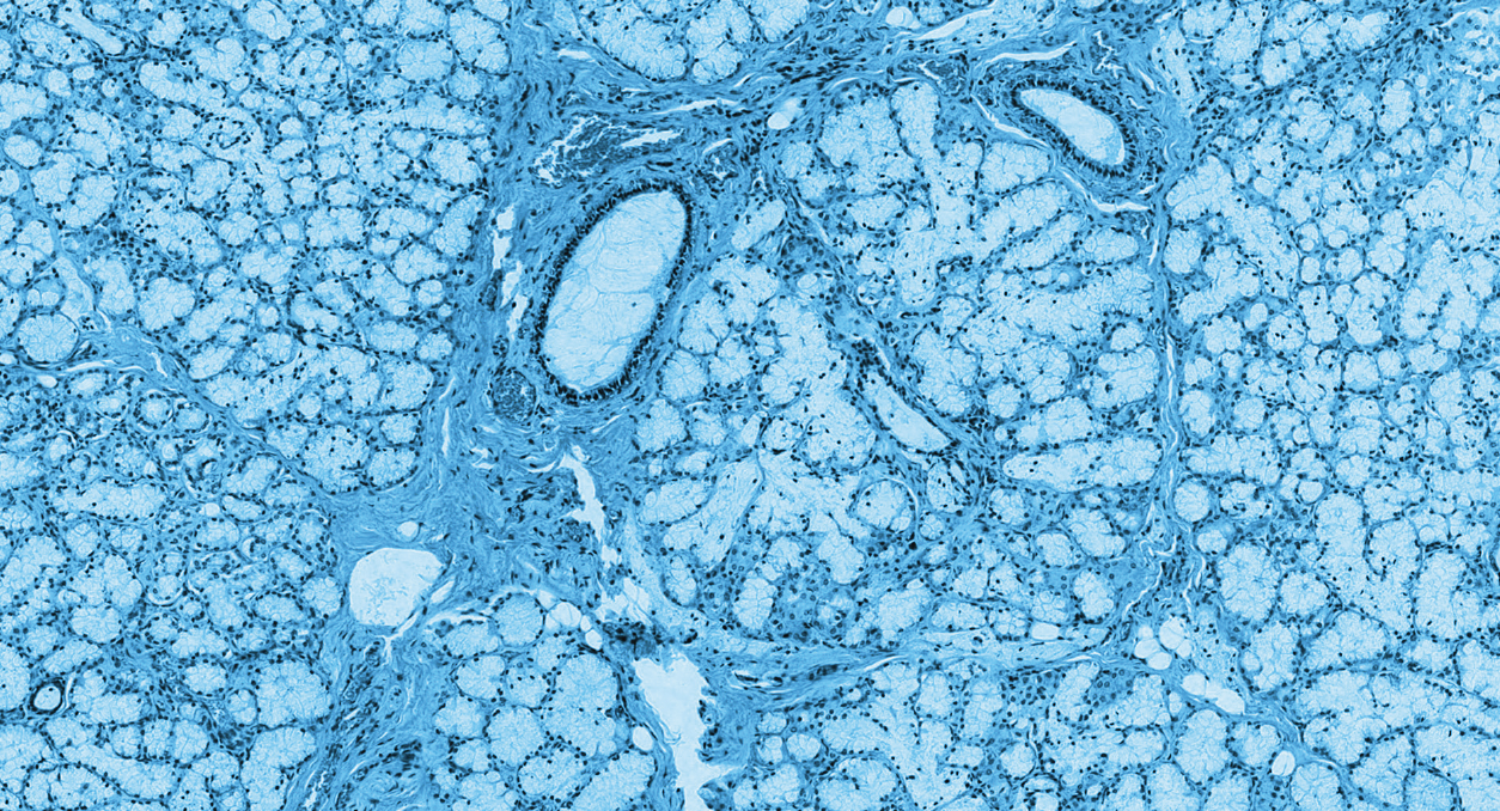

Toward microbe-friendly diets for optimum health outcomes

The expanding notion of human health—and the interconnected relationship between our diet, well-being, and microbiome—will deepen and open up new opportunities to design food that resists spoilage, tastes better, and targets the nourishment of both bodies and microbes.